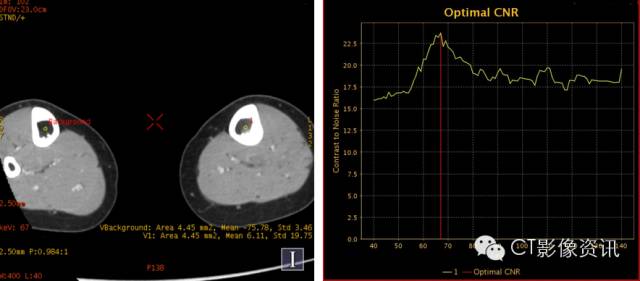

增强扫描,CNR 67kev最佳单能成像。